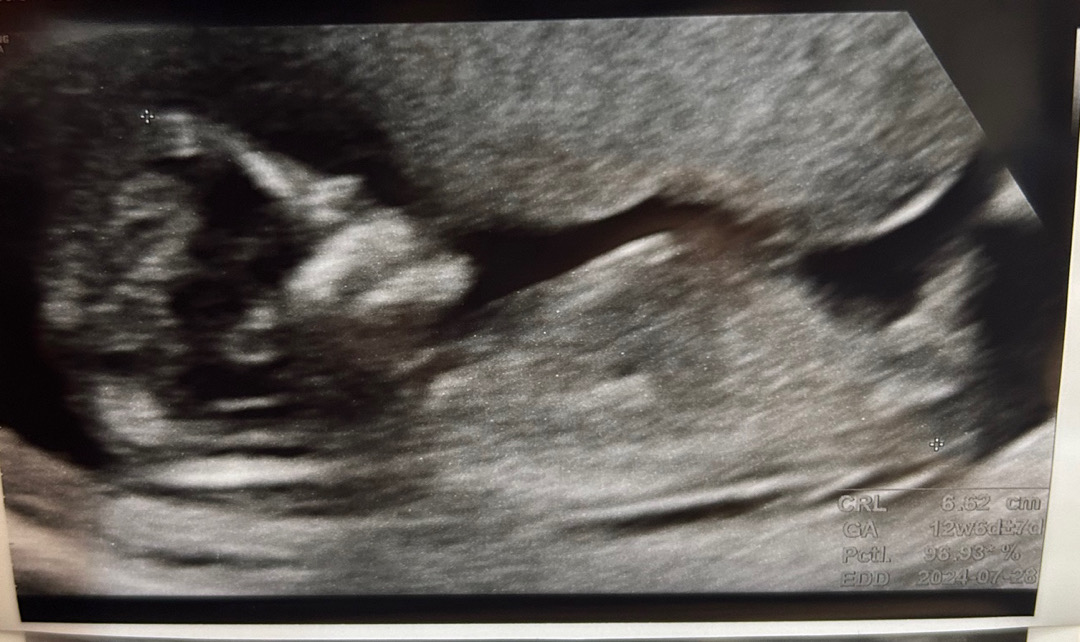

12주6일 각도법 힌트있을까요? ㅠㅠ

첫 아가라서 성별이 너무 궁금해서요 ㅠㅠ 짐작가시는 성별 있을까요? ㅠㅠ